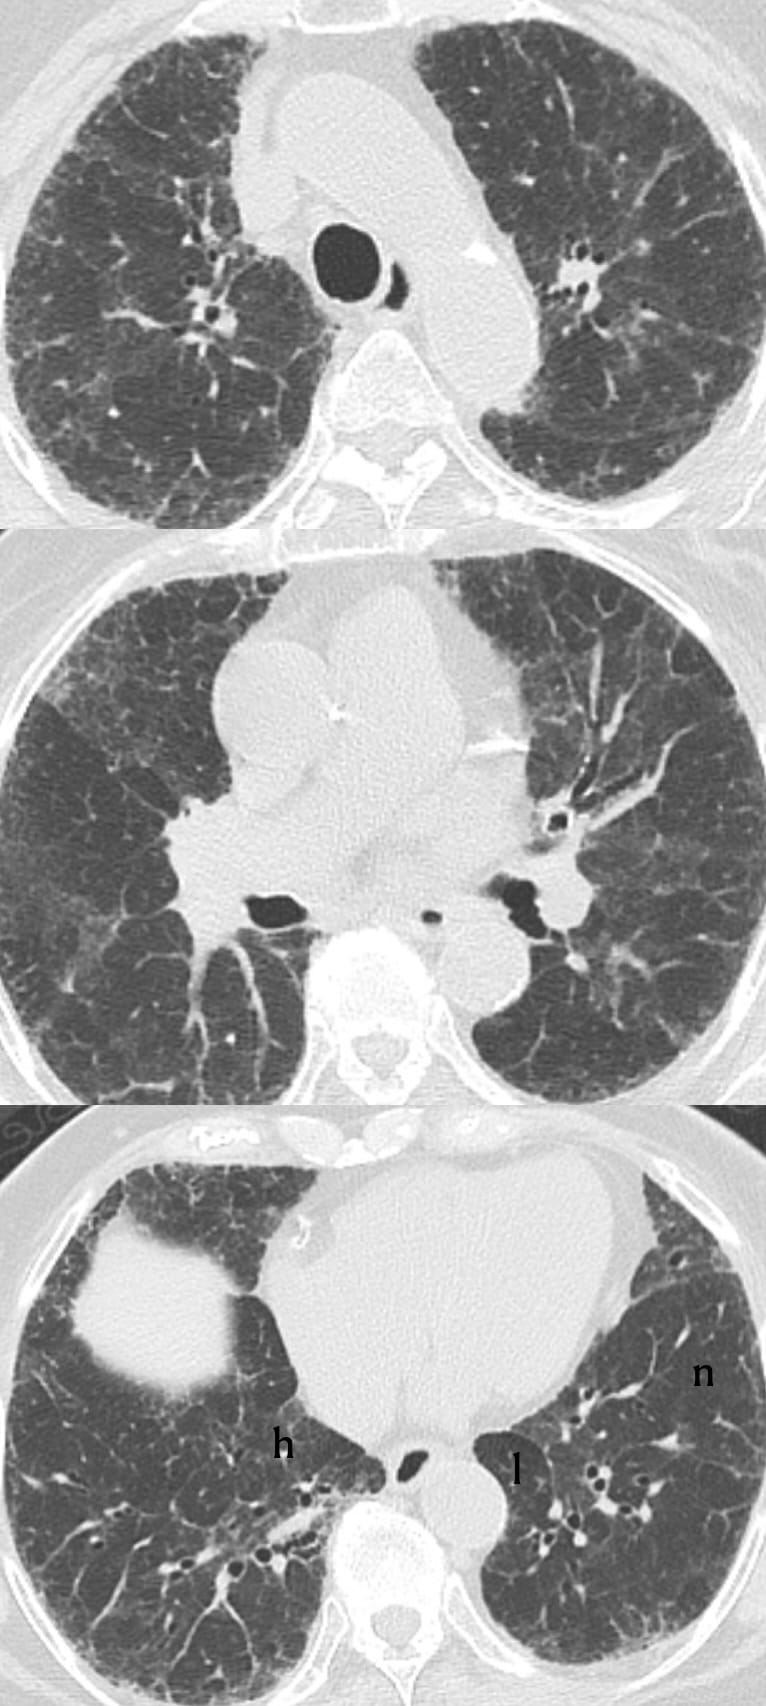

- Usual Interstitial Pneumonia